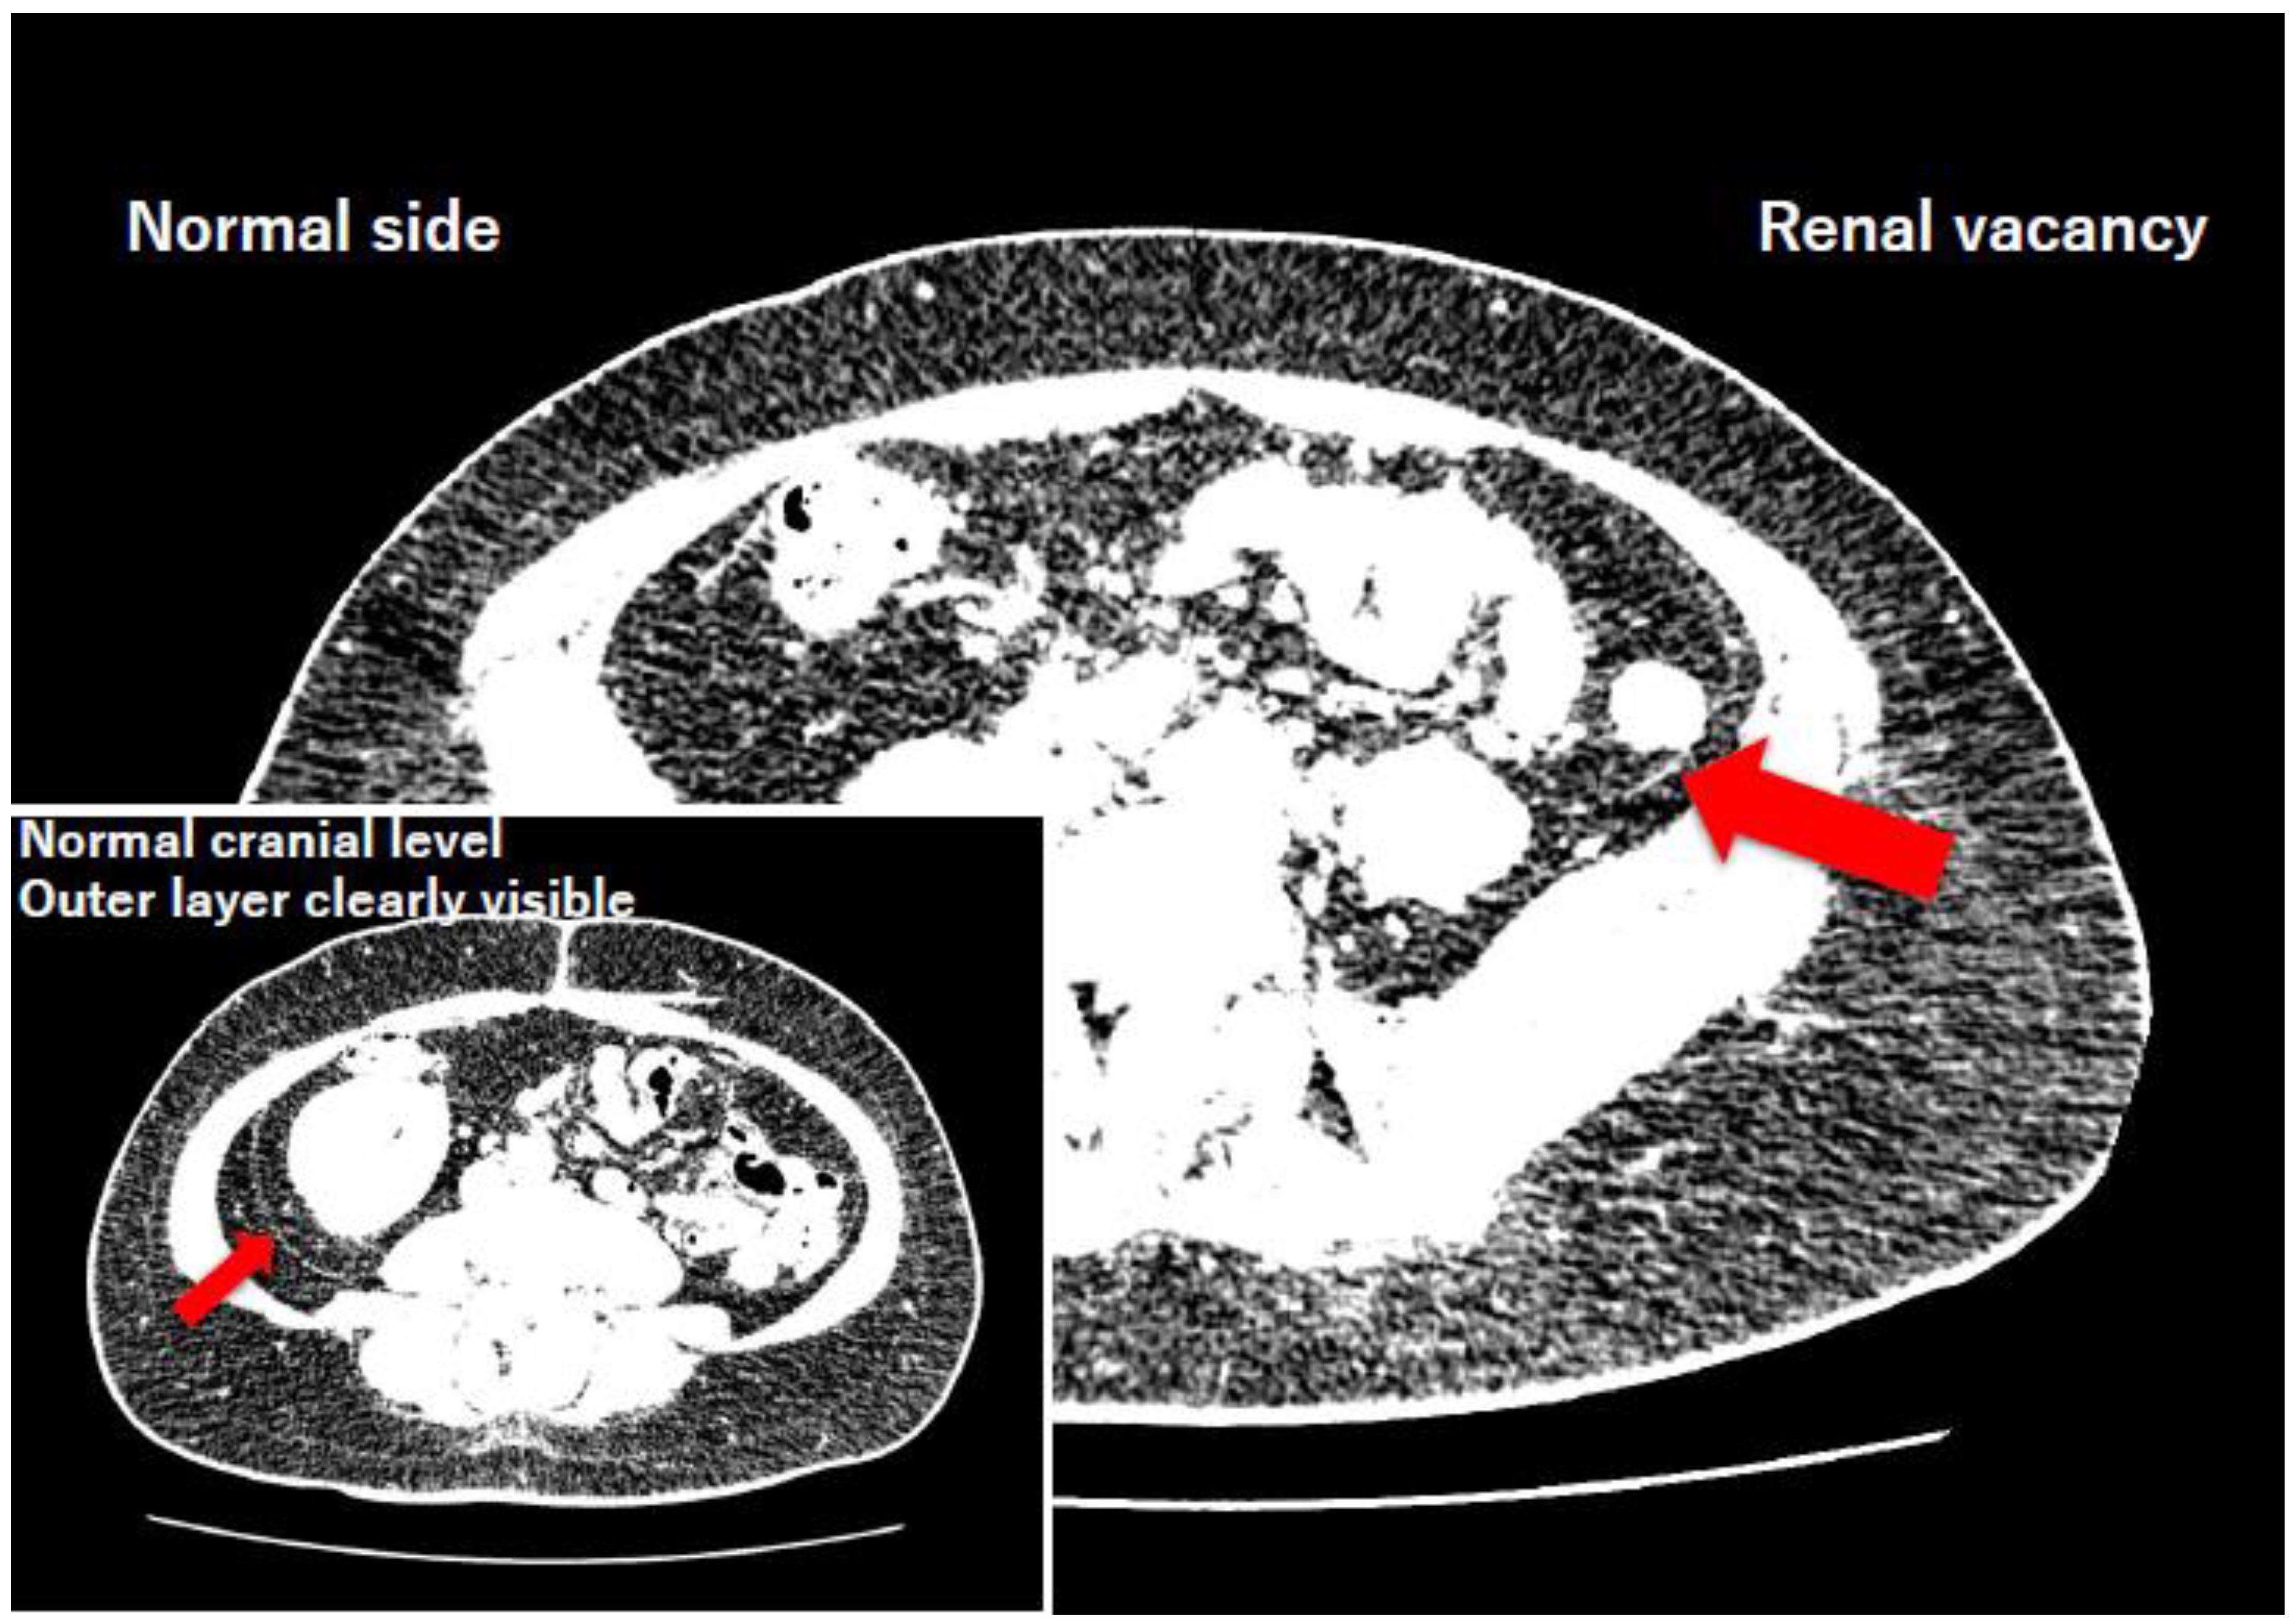

- Clinical contradiction: Historical macroscopic dissections suggest complete fascial agenesis in the absence of a kidney (Tobin, 1944), whereas modern cross-sectional imaging reveals that the normal posterior renal fascia is a bilaminar structure (Raptopoulos et al., 1986). How the connective tissue meshwork behaves in the developmental absence of the primary organ thus remains a contentious and unresolved question.

3.1. Radiological Subtraction Experiment (Adult Renal Vacancy)

| Case | Age/Sex | Radiological Diagnosis | Adrenal Morphology | Fascial Thickness (Vacancy Side) | Fascial Thickness (Normal Side) | Difference (Δ) |

| 1 | 53/F | True Left Renal Agenesis | "Pancake" (lying-down) | 1.49 mm | 1.88 mm | −0.39 mm |

| 2 | 47/F | Severe Left Renal Dysplasia / Involution (renal nubbin) | Normal | 1.46 mm | 1.82 mm | −0.36 mm |

| 3 | 89/M | True Left Renal Agenesis | "Pancake" (lying-down) | 1.62 mm | Excluded* | N/A |

| Mean | 1.52 mm | 1.85 mm | −0.38 mm |